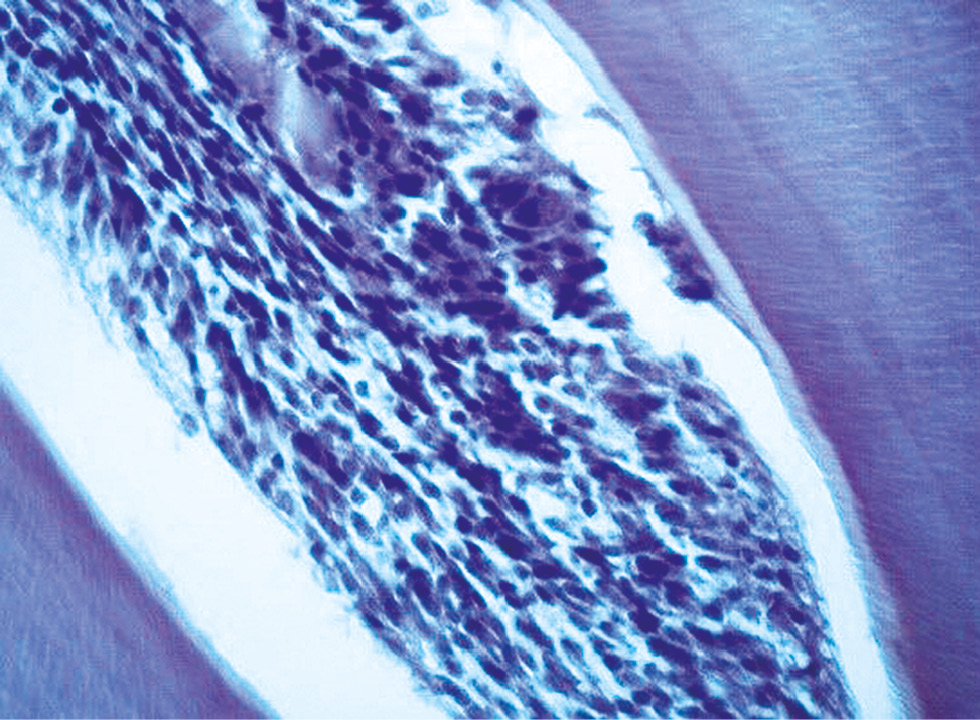

In Group 3 (1,400 mW/cm2, 3-second exposure), histologic architecture was preserved on Day 1 (Fig. 1), and findings were largely within normal limits. However, heterogeneous blood filling of the pulp microvasculature was noted. The odontoblast layer appeared thinned and sparsely populated. Capillary walls exhibited plasmorrhagia, with occasional stasis in the lumen; endothelial cells remained intact. On Day 3, mild perivascular lymphocytic infiltration was observed in the pulp stroma (Fig. 2).

Fig. 1. Transverse histological section of a tooth (third experimental group, day 1). Hematoxylin and eosin staining; ×100.